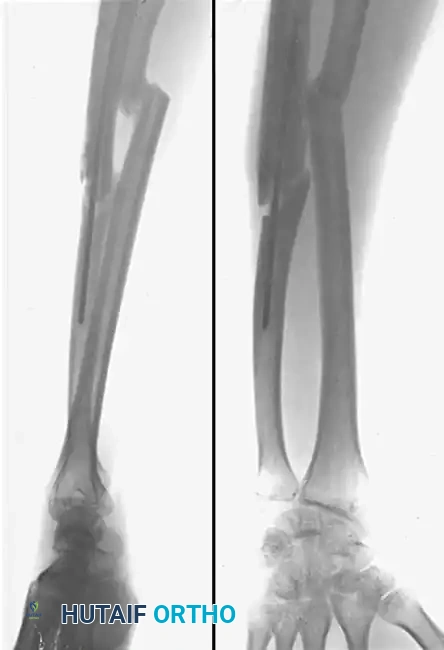

Image

Figure B: Postoperative radiographs taken 6 months after corrective osteotomy. Solid union has been achieved with normal skeletal alignment. The radius and ulna have been rigidly fixed with 3.5mm compression plates, and the structural defects were successfully managed with autologous iliac crest bone grafts. The interosseous space and radial bow are fully restored.